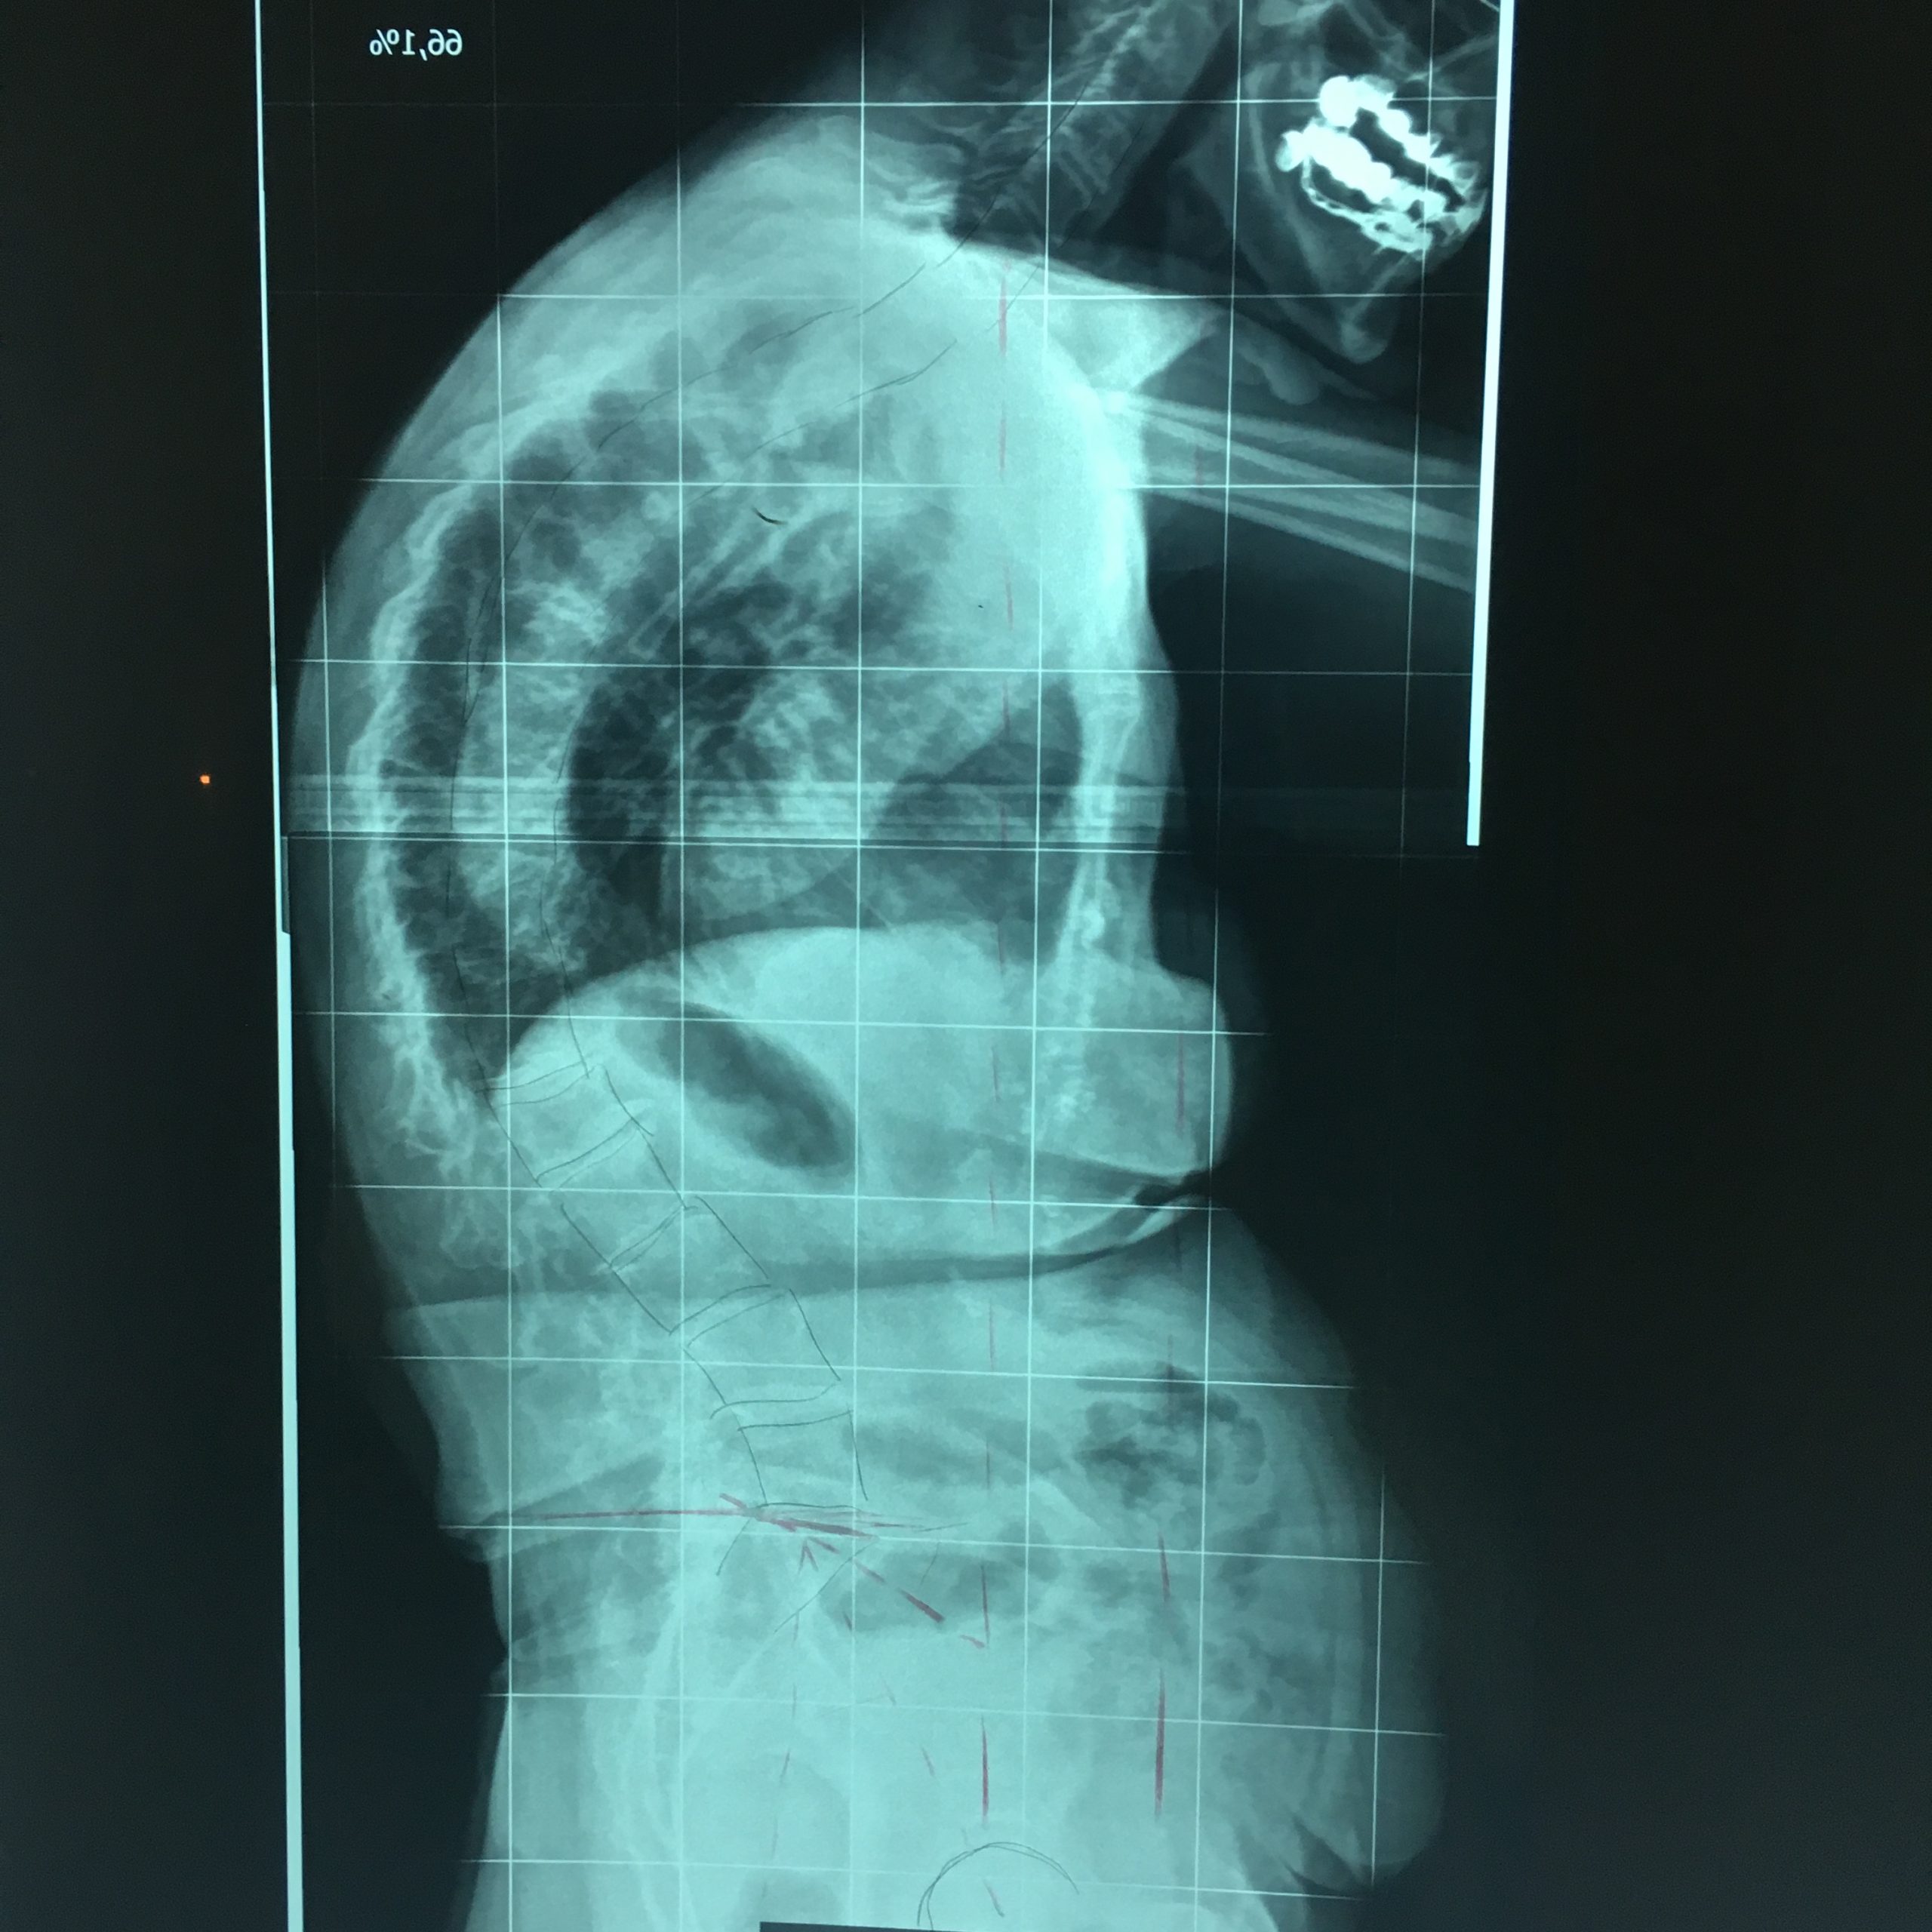

2. Η χειρουργική επέμβαση αποσκοπεί στο να επιτευχθεί η ισορροπία της Σ.Σ. κατά το μετωπιαίο και πλάγιο επίπεδο, δια της αποκατάστασης στο φυσιολογικό βαθμό της Θωρακικής Κύφωσης και της Οσφυϊκής Λόρδωσης (εικ.11).

Εικόνα 11 (α, β, γ, δ)

Προσθιοπισθία και πλάγια ακτινογραφία της πάσχουσας σε όρθια στάση. Παρατηρείται η μεγάλη παραμόρφωση και αστάθεια (α,β) της Σπονδυλικής Στήλης προ της χειρουργικής επέμβασης και η επιτευχθείσα διόρθωση και σταθεροποίηση αυτής (γ,δ) δια της χειρουργικής επέμβασης.

Η διόρθωση των σκολιωτικών και κυφωτικών κυρτωμάτων επιτυγχάνεται σε ποσοστό 30%-60%, εξαρτάται δε σε μεγάλο βαθμό από την αιτιολογία, το μέγεθος, την ελαστικότητα του κυρτώματος και τη χειρουργική τεχνική που χρησιμοποιήθηκε.